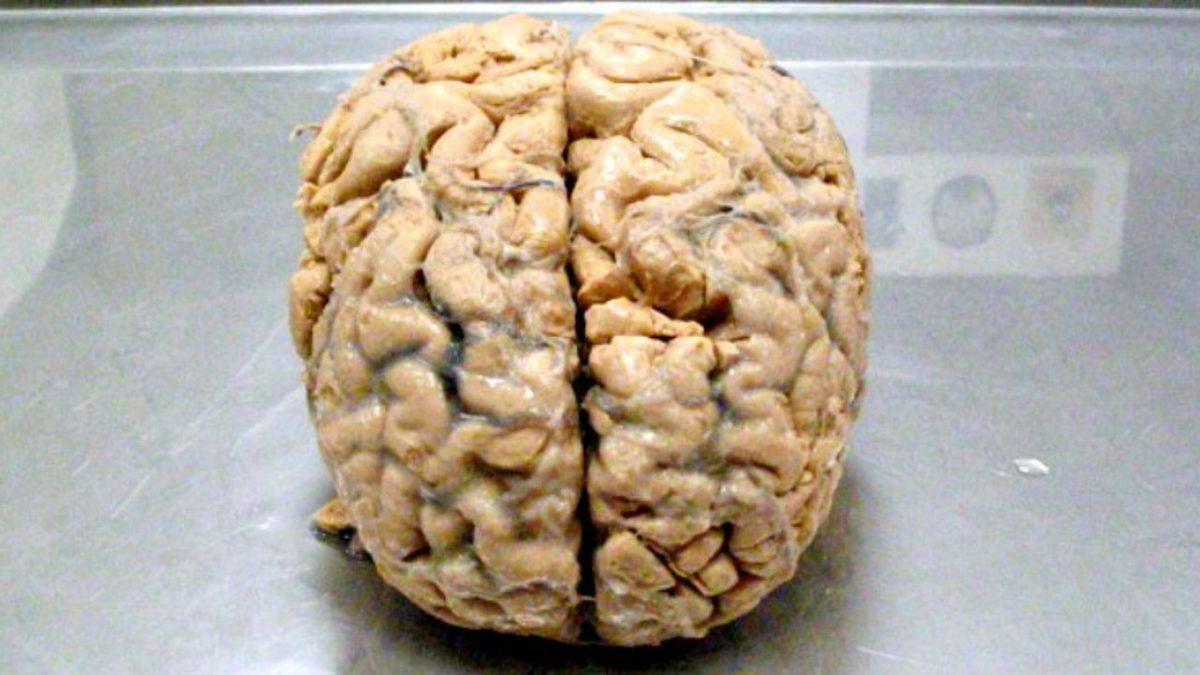

Bu şikayetinin neyden kaynaklandığını bulmaya çalışan doktorlar, yaptıkları beyin taramasında kafatasının büyük kısmının sıvıyla dolu olduğunu gördü. Şaşırtıcı şekilde gerçek beyin dokusunun sadece ince dış tabakası yerindeydi.

Ancak beyninin iç kısmının neredeyse tamamı aşınmış durumdaydı.